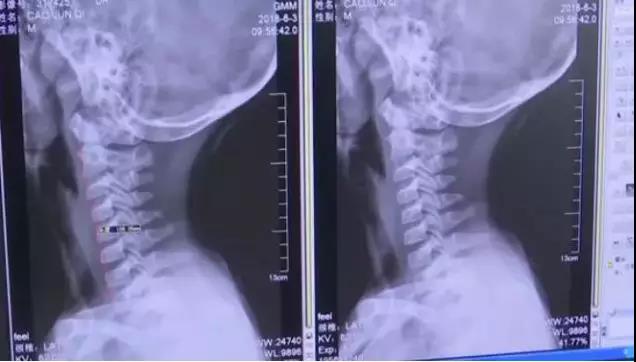

经过CT检查发现,这名男童的颈椎出了问题。

正常人颈椎带前曲弧度的,男童的颈椎已经是一条直线了!才9岁!

查其原因,这名男童一年多来,经常低头长时间玩手机。医生介绍说,低头看手机时,颈椎所承受的重量是垂直时的3倍,如果姿势不当,可能让颈椎承受多达27公斤的重量。